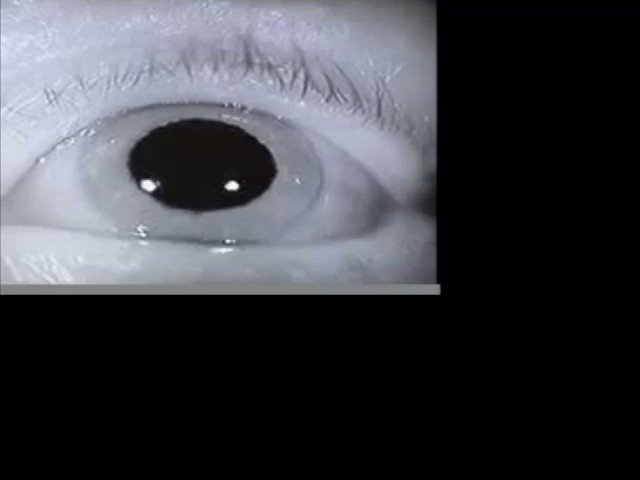

7/ Image

Downbeat nystagmus

i) evoked by looking down and laterally

ii) no suppress by visual fixation

iii) vestibulocerebellar involvement

via: Moran CORE